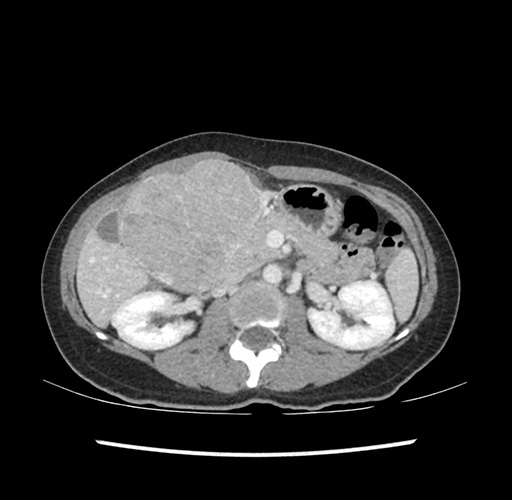

Imaging Analysis

Look through the patient's CT scan to identify any areas of concern for the necessary procedure.

Based on your CT findings, which issue(s) would give reason for "planned slowing down moment(s)" in this case?

Considering a standard left lateral sectionectomy procedure, what step(s) of the operation would you do differently in this case ?